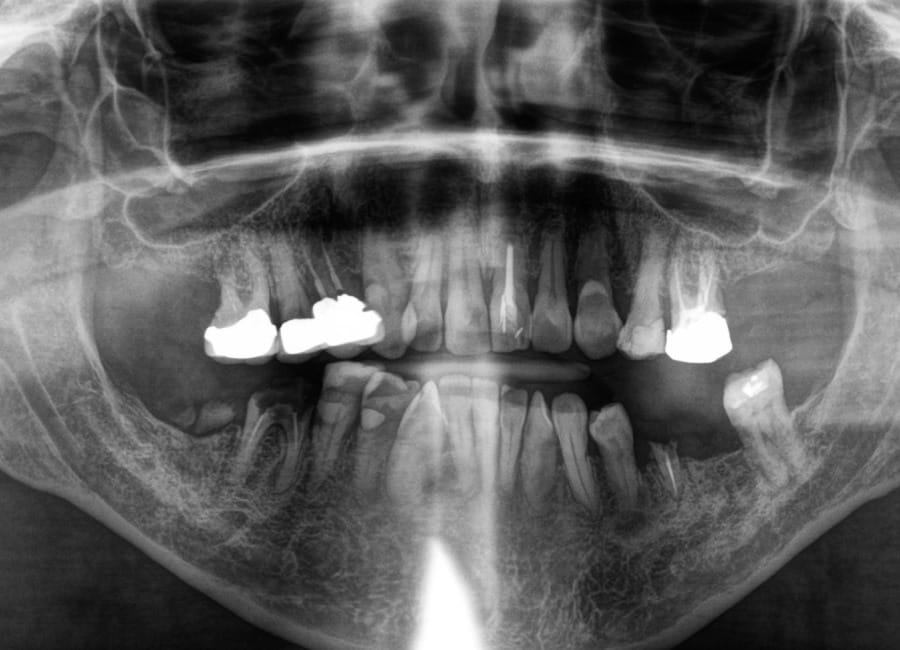

Natalie arrived at Wimpole Street Dental Clinic facing an extremely challenging dental situation. She had several missing and damaged teeth, infections in the bone, and significant bite issues caused by a long-term tongue habit. On top of that, she was a smoker and had developed a strong dental phobia over the years, making it difficult for her to seek help sooner.

Natalie’s treatment began with a comprehensive clinical assessment, including a review of her medical and dental history, a full examination, and analysis of her functional difficulties such as her tongue habit and altered bite. A 3D cone-beam CT scan was then taken to assess bone quality and volume, identify areas of infection, and map important anatomical structures to ensure safe implant placement.

Alongside this, a digital intraoral scan and detailed photographic records were captured. These provided accurate models of her teeth and bite, as well as valuable information about facial proportions and smile aesthetics. Together, these records ensured that planning would address both the functional and cosmetic aspects of her rehabilitation.

All data were transferred into digital treatment planning software, allowing virtual placement of implants and collaboration with the dental laboratory before surgery. This enabled careful evaluation of long-term outcomes and ensured the design of provisional and final prosthetics could be completed with precision. Following these discussions, the decision was made to proceed with the Fixed-Teeth-in-a-Day approach using the All-on-4 technique.